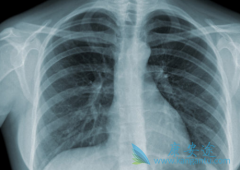

目前在中国,肺癌发病率在恶性肿瘤的首位,大约为46.08/10万,占所有恶性肿瘤19.59%。而且因为缺少前期发现的有用手法,大都病人在就诊时就已经是晚期。 肺癌晚期 的症状有哪些?据专家表示,肺癌患者中有5%-15%的不会出现明显症状,只有在做胸部影像检 ...

肺癌是一种让人恐惧的癌症,因为它的发病率和死亡率增长都非常快, 肺癌晚期 对人群的健康和生命威胁非常大,是一种恶性肿瘤。近些年来,许多国家都有报道,肺癌的发病率和死亡率都明显增高,并且男性肺癌的发病率比女性要高。   目前为止,肺癌的病因 ...

大家对肺癌的印象可不大好,因为这是种非常恐怖的癌症,肺癌是发病率和致死率第一的癌症,是“杀伤力最大的肿瘤”。因肺癌早期无明显症状和特异性,导致很多人发现时已是中晚期。那么,肺癌晚期有多可怕? 肺癌晚期 临终前症状往往比较明显,主要包括局 ...

一说到癌症,大家都是非常恐慌的,毕竟以现在的科学技术来说,治疗癌症还是有一定的困难,对于每个人来说,癌症是非常可怕的一种疾病。而肺癌是发病率和死亡率增长最快,对人群健康和生命威胁最大的恶性肿瘤之一,男性肺癌发病率和死亡率占说所有恶性肿 ...

大家之所以害怕肺癌的原因是, 肺癌早期症状 非常不明显,这就导致很多患者被发现时已经是中晚期了,而且治疗的难度就比较大了,肺癌如果能在早期被发现,其实远没有大家想象的那么可怕。一般有数据显示肺癌患者如果能在早期被发现,一般五年生存率都能 ...